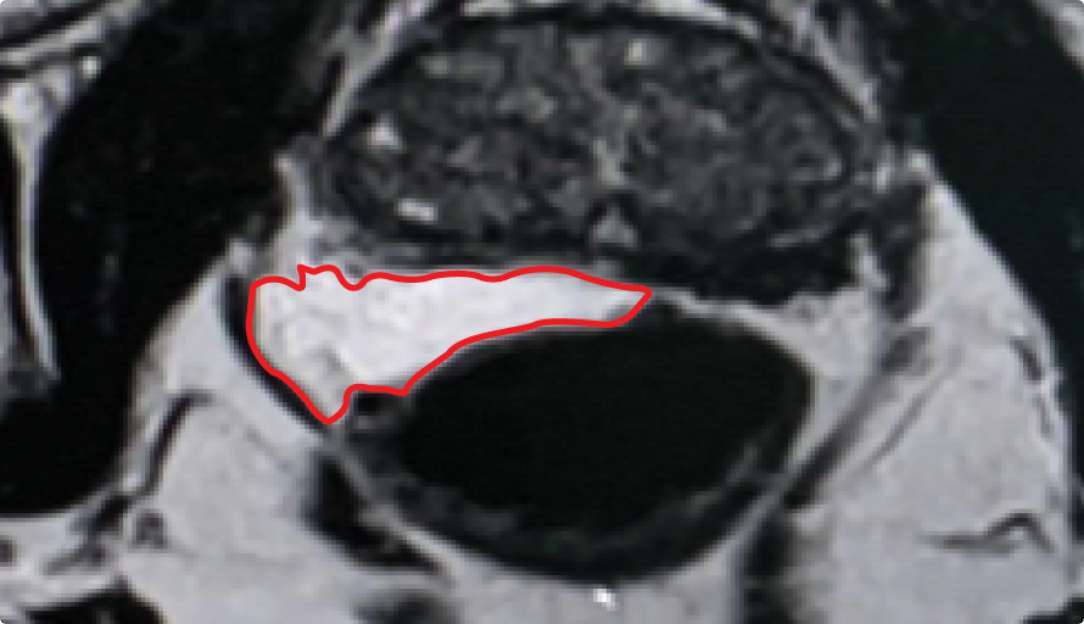

PATIENT EXAMPLE SHOWING

STABLE SEPARATION DURING RESORPTION

Results may vary.